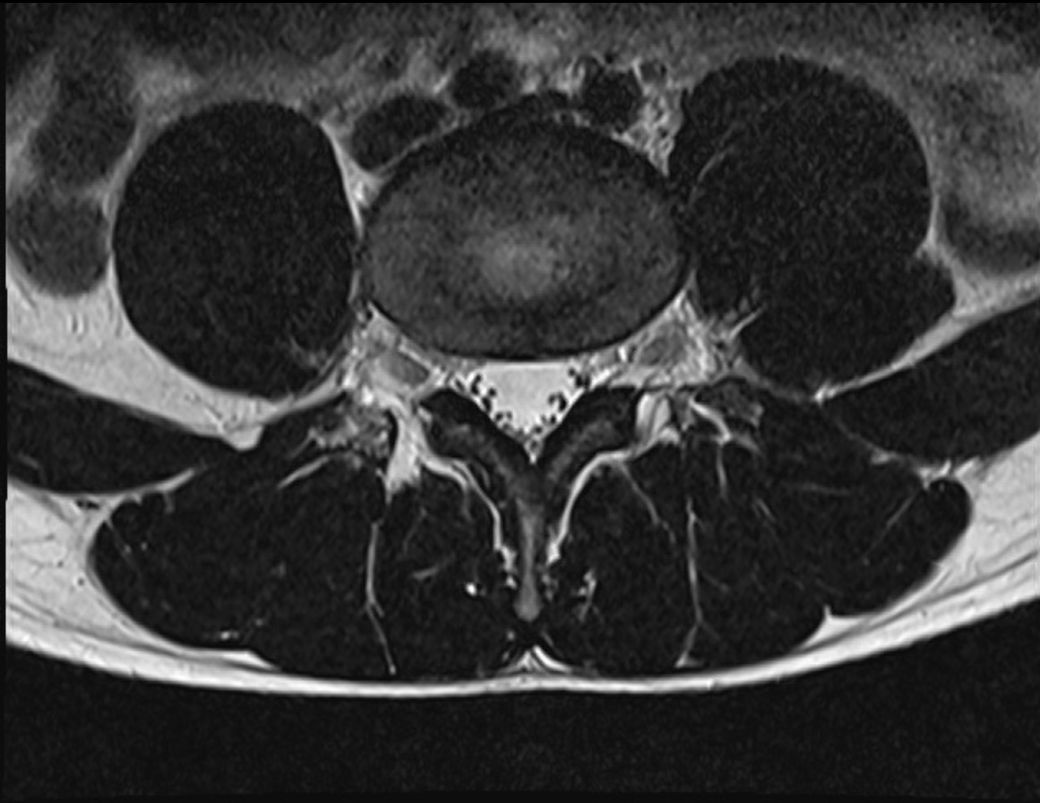

병원마다 MRI 결과를 다르게 보는 이유로는 디스크가 살짝 튀어나와 있지만 신경을 누르지는 않거나 그 경계에 있다면 그럴 수 있으며 올려주신 MRI사진 같은 경우 단면 사진으로 단면사진만으로는 평가하기 힘들 것으로 생각되며 일단 올려놓으신 영상만 보았을때는 큰 문제는 없는걸로 보이며 자세한 상태는 영상을 가지고 전문 병원에 방문하시어 제차 검사 받아보시는게 좋을 것으로 생각됩니다.

올려주신 사진상에서 허리 아래부위에 존재하는 디스크가 약간의 돌출이 보이는데요, 신경을 압박하는 것처럼 보이지는 않습니다.

디스크 돌출이나 경미한 추간판 탈출증으로 보이는데요, 각 병원에서 견해에 따라 허리디스크로 진단하거나 하지 않는 것으로 보입니다.

어느 누가 맞고 틀리다가 아닌 각각의 진단기준에서 발생하는 차이로 보이기 때문에, 검사결과 뿐만 아니라 현재 증상도 참고하였을 때를 기준으로 진단을 한 것이 아닌가 생각됩니다.